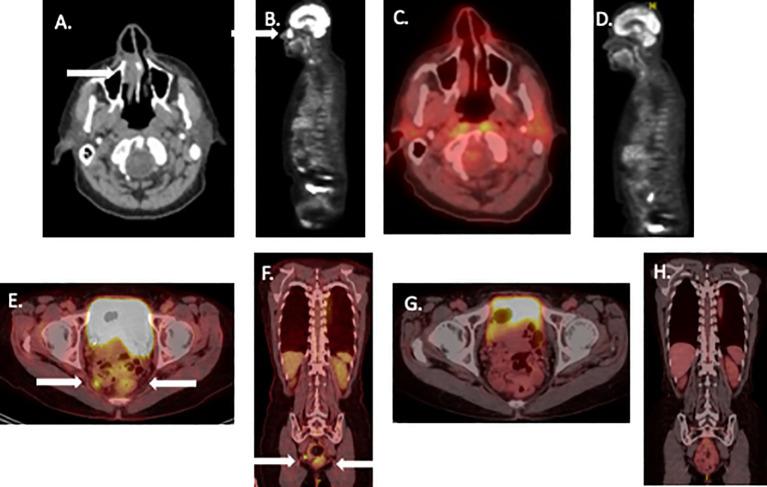

Neoadjuvant ipilimumab plus nivolumab therapy as a potential organ preservation strategy in mucosal melanoma: case report.

Mucosal melanoma represents an uncommon melanoma subtype. Wide excision has long represented the standard therapeutic approach. Unfortunately, there is a high relapse rate and mortality. Neoadjuvant therapy with ipilimumab plus nivolumab has shown significant activity in cutaneous melanoma. We present two cases of mucosal melanoma, each with potential regional dissemination, who were treated with neoadjuvant immunotherapy with minimal toxicity. Both patients were closely monitored and achieved radiologic and pathologic complete responses. These patients were able to avoid radical surgery and related functional consequences. Both patients remain recurrence-free with protracted follow-up. The potential usefulness of neoadjuvant immunotherapy as an organ preservation strategy in mucosal melanoma deserves further evaluation in prospective clinical trials.